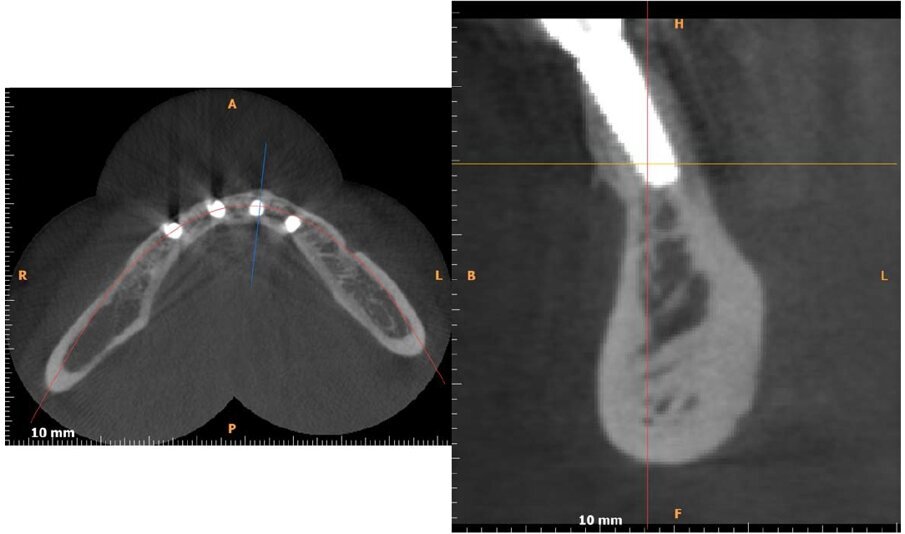

Viene presentato il caso di un paziente (maschio, 57 anni) inquadrato nosologicamente come ASA 1 e riferito alla nostra osservazione per la riabilitazione implantoprotesica di un’area edentula in mandibola anteriore (Fig. 1). Le indagini radiografiche di 1° e 2° livello (ortopantomografia e CBCT) evidenziano una marcata atrofia ossea di tipo combinato (classificabile come grado 3 sec. Seibert) che controindica l’inserimento di impianti osteointegrati (Fig. 2). Considerato il notevole riassorbimento della cresta ossea, per ridurre il rischio di incidenti intraoperatori e poter pianificare al meglio l’intervento chirurgico, viene simulato il posizionamento di 4 impianti Resista IA3413 (Resista, Via F.lli Di Dio, 68 – Omegna, VCO) tramite il software per ricostruzione tridimensionale Real Guide Ver. 5.0 (3Diemme, Como).

Fig. 3 - Esame CBCT preoperatorio che evidenzia l’anatomia ossea residua.